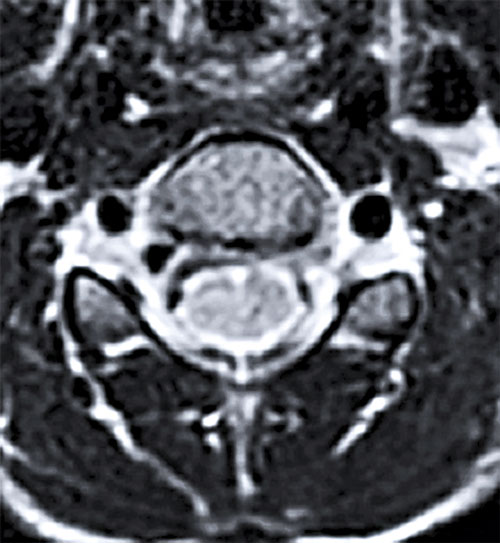

Omfattande mikrobiologisk utredning genomfördes, inklusive prov från likvor, blod, feces m m. Nasofarynxaspirat kontrollerades 10 dagar efter det att han först insjuknat och utföll positivt för enterovirus. Senare typning påvisade EV-D68. MR visade fokala signalförändringar i pons och medulla oblongata samt långsträckta signalförändringar över flera nivåer i ryggmärgens gråa substans utan kontrastmedelsupptag som vid en långsträckt central myelit (Figur 2).

Upprepad MR-undersökning efter drygt 2 veckor visade att signalförändringarna i ryggmärgen hade gått i regress men att det tillkommit kontrastupptag i cervikala och lumbala nervrötter (Figur 2). Neurofysiologiska undersökningar med EnEG, EMG och motoriska reaktionspotentialer 1 månad efter insjuknandet visade tecken på uttalad påverkan av nedre motorneuron i undersökta myotom på vänster sida och en generellt förlängd central överledningstid till undersökta segment på samma sida, vilket talade för påverkan även på centrala motoriska banor.

Figur 2 (fall 2). Vid initial MR-undersökning visade T2-viktad sekvens långsträckta signalförändringar i hela ryggmärgen (första bilden) samt fokalt i bakre delen av pons (andra bilden). Axialt i höjd med C2 påvisades engagerad grå substans (tredje bilden). Vid uppföljande MR-undersökning visade T1-viktad sekvens över halsryggmärgen (sista bilden) endast kontrastladdning i nervrötter.